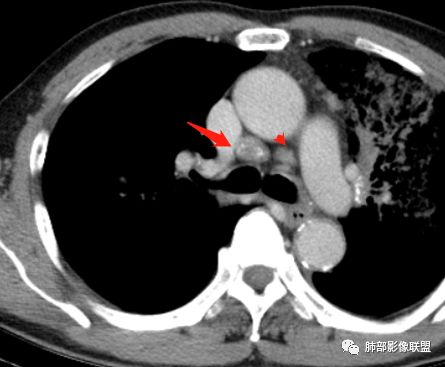

背段支气管有问题,局部有结节

左肺上叶病灶长轴与支气管走形一致,提示沿支气管分布病变,倾向于炎性,大家可能怀疑这个病例是来源于胸膜下为主的,胸膜下来源首先整体是来源于胸膜下,与胸膜下之间没有间隙,而这例与胸膜下有间隙。而且这个病变是沿支气管朝外蔓延的,而胸膜下来源的是朝内蔓延的,唯一给我们错觉的是靠近纵隔胸膜这个地方有问题。但是靠近纵隔胸膜这个位置实变不是靠近胸膜实变,它边缘收缩的,没有膨隆的迹象。我们看到里面支气管直达远端稍扩张,是以中央间质为主、小叶间隔朝外蔓延,有间质也有实质病变,走向是沿中央间质方向走的,我个人倾向炎性病变。    问题是右下叶病灶怎么解释?右隔上、右肺门各有一个结节。这个病人有急性咳嗽、胸痛的病史,还有糖尿病病史,周围渗出比较明显,应该警惕炎性病变,要警惕克雷伯杆菌、结核、金葡菌霉菌,因为糖尿病人经常好发这些病菌感染。那么右下叶病变怎么考虑?能不能一元论?    左肺病灶是一个急性渗出为主的病变,一个急性感染的迹象;右肺下叶背段结节,没有看到支气管,增强图支气管壁增厚,局部小结节,呈分叶状,支气管堵塞,没有粘液栓样指套样改变,但是里面有强化,我倾向于癌,其次待排结核。我还是倾向于癌的可能性,恶性可能性大一些,可惜我看不到支气管腔内。还考虑有没有淀粉样变性的问题,弥漫钙化灶最常见的一个是结核,另一个是淀粉样变性。叶段支气管壁有弥漫增厚的迹象。所以淀粉样变性跟结核都要考虑。

鳞癌起源于支气管粘膜,是气道中最常见的恶性肿瘤,易造成支管壁增厚,并突入腔内形成结节,造成狭窄、阻塞或截断;早期鳞癌表现为沿支气管生长的梭形结节或局限性增厚,辖区内常出现阻塞性炎症,这样的病灶赢多平面重建并仔细观察支气管改变;如果有支气管壁偏心性增厚伴管腔狭窄或腔内结节形成,都要想到早期鳞癌的可能性,复查或内窥镜检查是必要的。

鳞癌好发于中老年人,与吸烟关系密切,如果发现不易吸收的,或同一部位反复无常局限性肺炎,我们应当仔细观察支气管壁的病变除外阻塞的可能;该病例右肺下叶背段及左肺上叶支气管有肿块及管壁的增厚,应当想到恶性可能。

1.右肺下叶支气管壁增厚,后壁为主,且显示壁外结节,未见异常强化。这样的结节和蔓延方式一般会高度怀疑气道来源的恶性肿瘤,如鳞癌、粘液表皮样癌、腺样囊性癌等。可惜没有相应病理学资料支持。